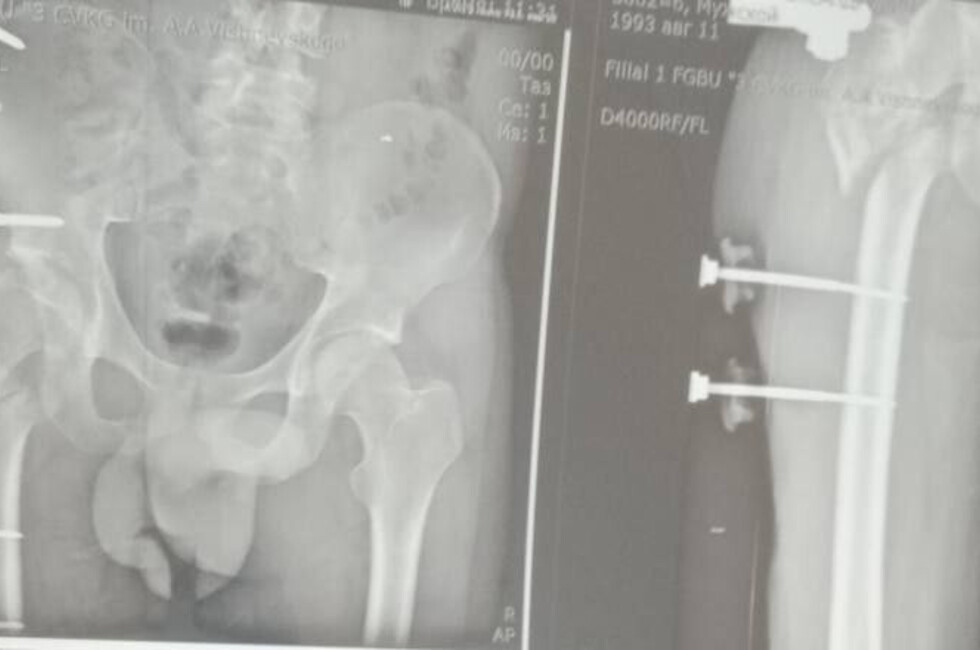

Сержант 1993 года рождения, мобилизованный 25 февраля 2022 года, получил тяжелое ранение правого бедра 28 августа 2022 года под ракетным обстрелом на Херсонщине. За три с половиной года он прошел лечение в десяти госпиталях, включая Москву и Санкт-Петербург. В июле 2024 года боец, награжденный медалью «За отвагу», был уволен по здоровью. Из-за множественных операций и повреждений его правая нога стала короче левой на 8–9 см.

«Требовалось чудо инженерной и хирургической мысли. Чудо произошло 5 марта 2026 года в Луганске. В Луганской республиканской клинической больнице бригада травматологов-ортопедов провела операцию, которая стала финальным аккордом этой долгой истории. Вместо стандартной замены сустава пациенту выполнили сложнейшее вмешательство с использованием ревизионных систем эндопротезирования, в ЛНР такую операцию провели впервые», — рассказала Пащенко.

Хирурги восстановили ось конечности и компенсировали укорочение, работая в рубцово-измененных тканях после множества предыдущих операций, устранив очаги инфекции и «собрав» сустав заново с помощью специальных ревизионных компонентов.